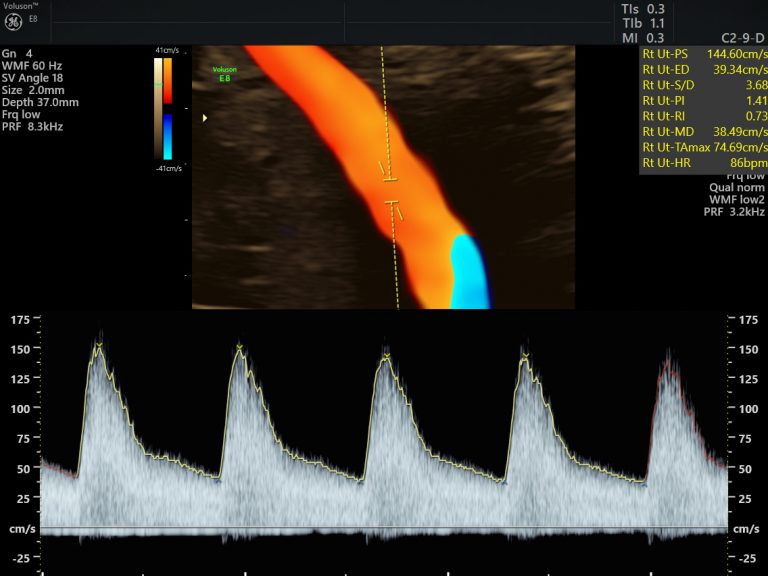

Small for gestational age babies are identified by obstetricians and referred to us for Growth and Doppler studies. This means we evaluated the adequacy of blood flow between the mom and placenta, baby and placenta as well as the flow into the baby’s brain. This information helps to plan the surveillance and delivery plan for the smaller baby meticulously. One always need to measure up the risk of being small intra-uterine, versus the risk of neonatal complications due to preterm delivery.